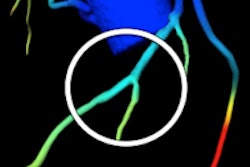

Image of CORE320 patient shows an occluded left anterior descending (LAD) stent on CT and catheterization, with the corresponding anterior wall defect demonstrated by CT perfusion and SPECT. Image courtesy of CORE320 investigators.The value of CT perfusion